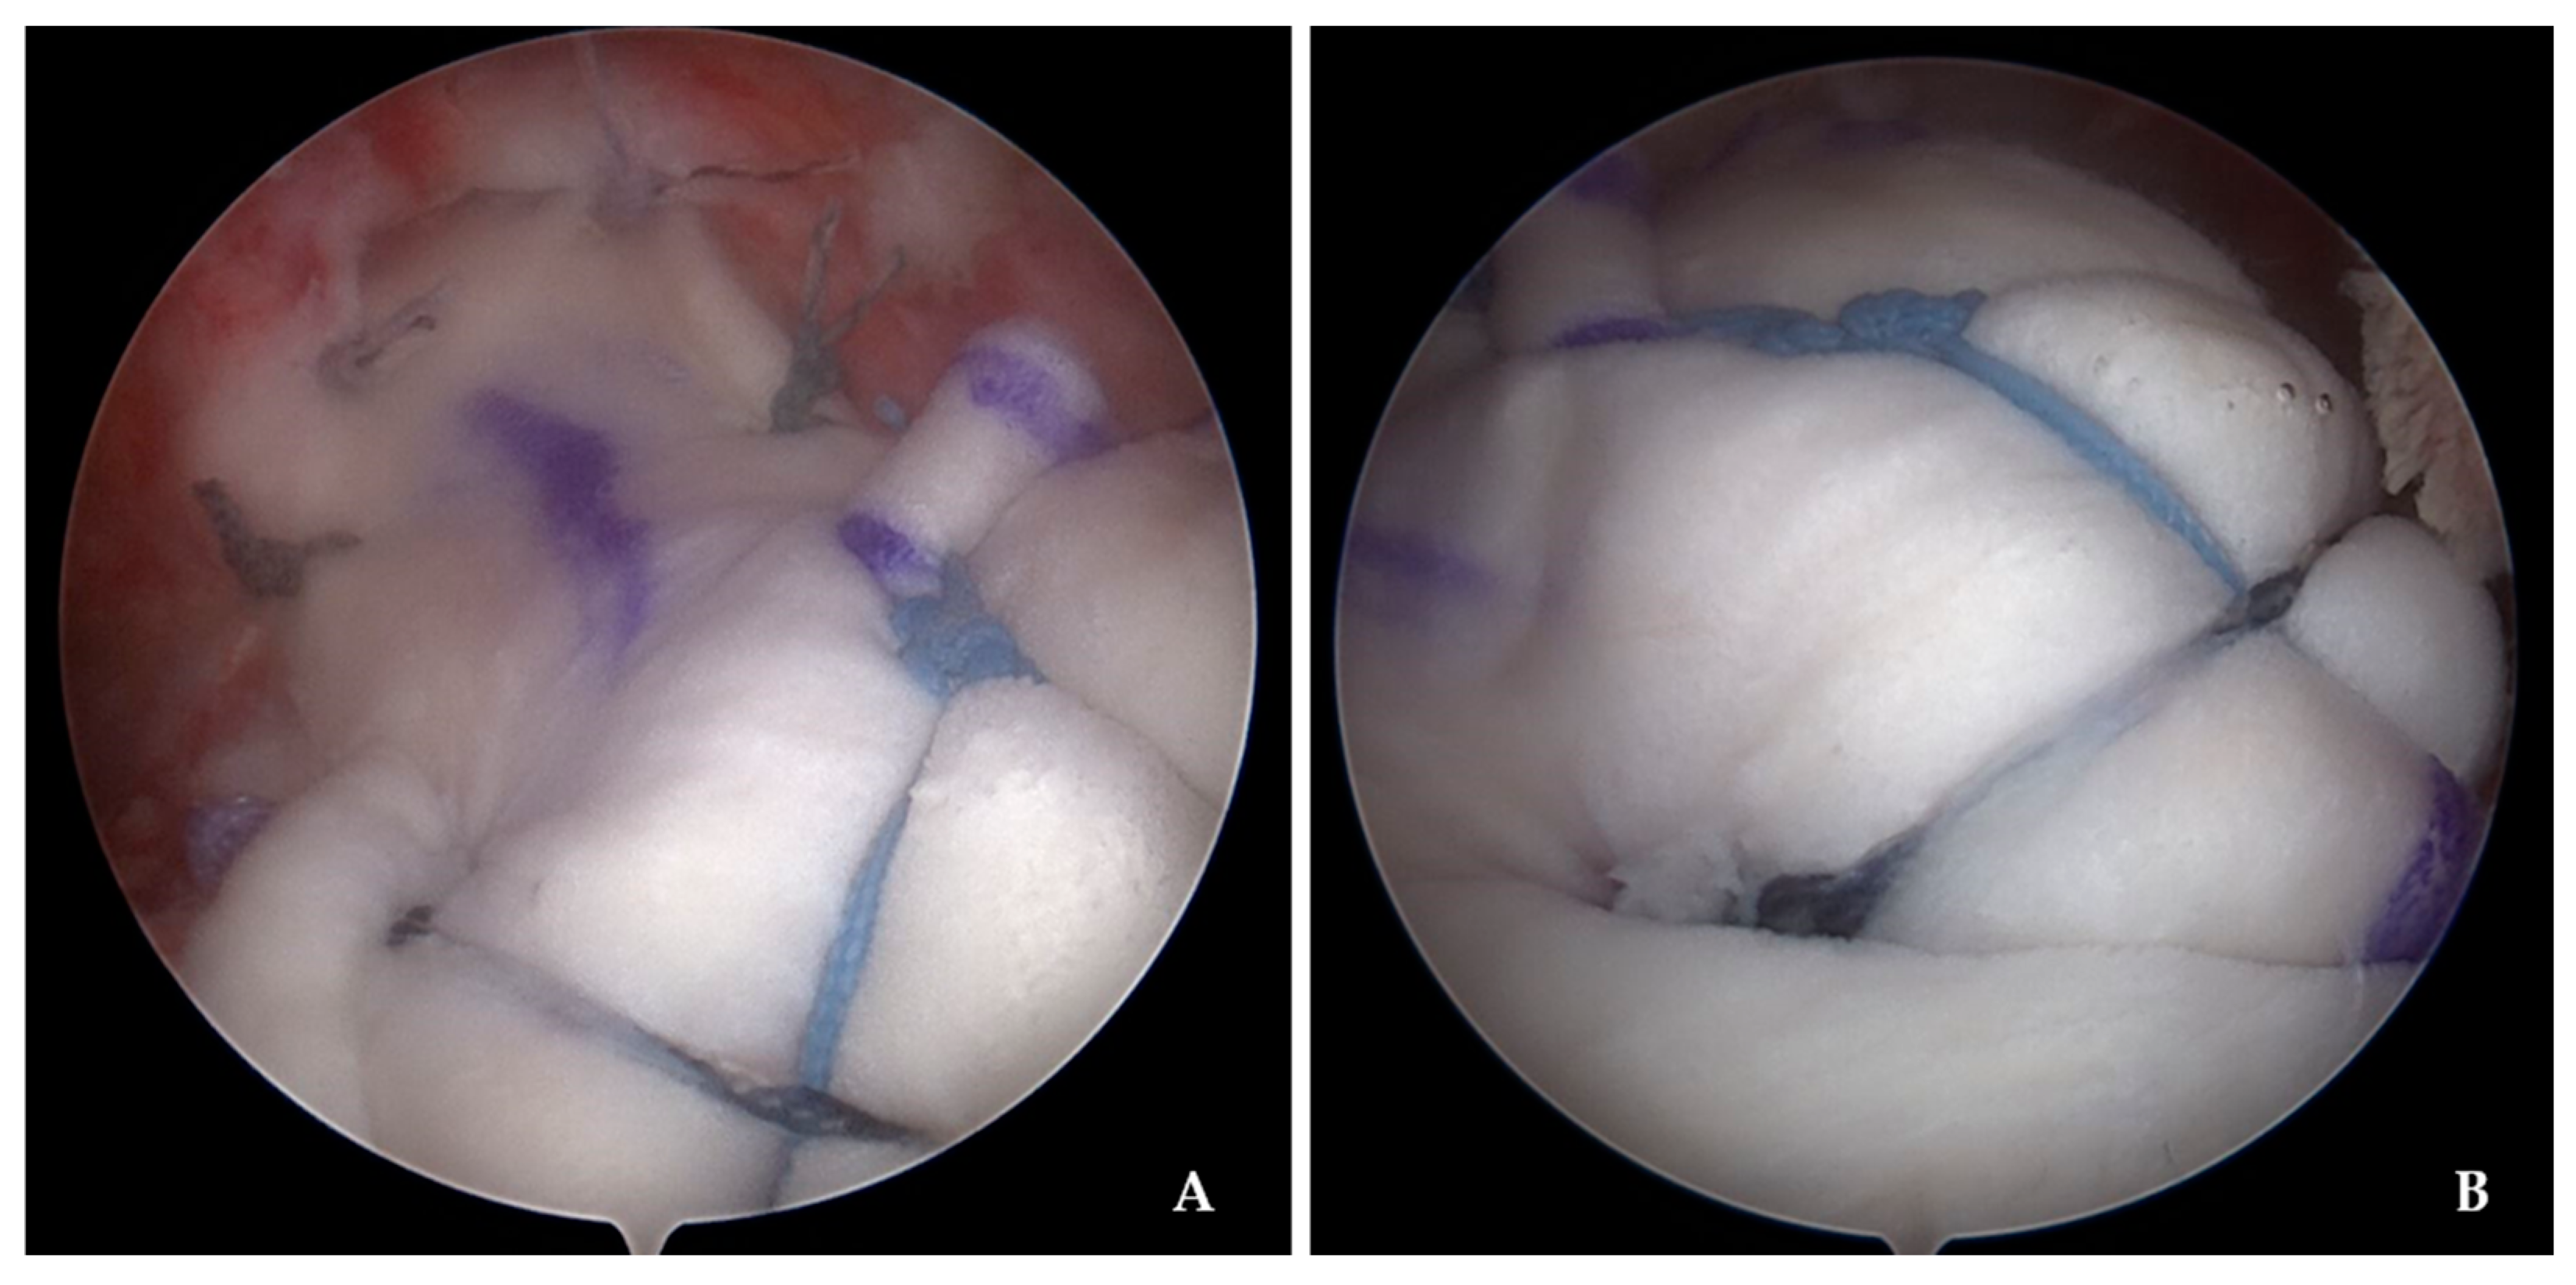

2.3. Surgical Procedure